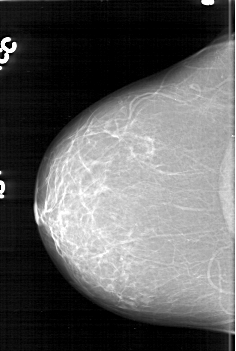

D_4195_1.RIGHT_CC

RIGHT_CC LINES 6316 PIXELS_PER_LINE 4231 BITS_PER_PIXEL 12 RESOLUTION 43.5 NON_OVERLAY